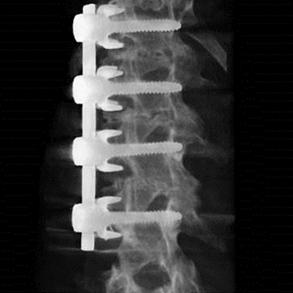

Spinal Fusion

Achieve spinal fusion procedures with improved visualization and less displacement. With automated support during the procedure, syngo Needle Guidance aids in significantly improving the accuracy of pedicle screw placement to help avoid repositioning.